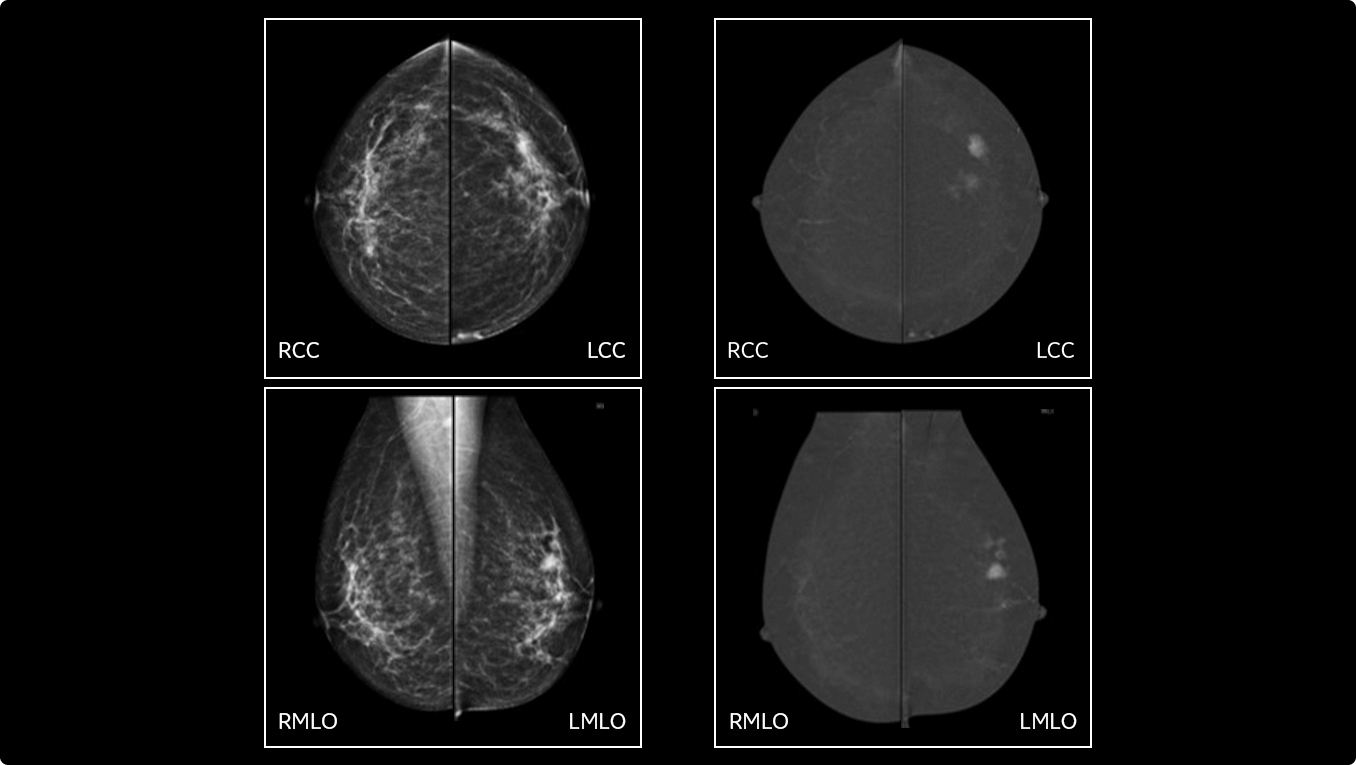

• Helps reduce the masking effect of fibroglandular breast tissue and increases the tumour signal1.

• Contrast agent highlights areas of unusual blood flow.

• Find lesions that cannot be seen on routine mammography6,7,8.

• Provide high specificity for low false-positives1.